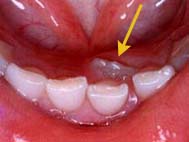

A、上の前歯の生え代わりは7歳前後で始まります。しかし転倒などの事故により早期に前歯を失うことがあります。早期に乳歯が抜けてしまっても、その下の永久歯の準備ができていませんので、やはり7歳前後にならないと永久歯は生えてきません。早期に上の乳前歯を失った場合、表面の口腔粘膜が厚く丈夫になり、永久前歯が生えようとしても粘膜を破ってこれないことがあります。通常の時期に乳歯が抜けた場合でも、本人が抜けた場所を気にして指で触っていたりとか舌で盛んになめていた場合にも同様なことが起こります。右の写真でもわかる様に歯ぐきが盛り上がり、指で触ると歯の形がわかるほどになります。このような場合には盛り上がった歯ぐきを部分的に切り取ることにより、永久前歯の萌出を手助けします。これを開窓と呼びます。適切な時期に処置をすると1ヶ月ほどで歯の半分程度も、萌出してきます。その他に乳歯が抜けてなかなか永久歯が生えてこない場合として、生えようとする永久歯の方向が悪い場合もあります。レントゲンで永久歯の方向を確認してもらって下さい。